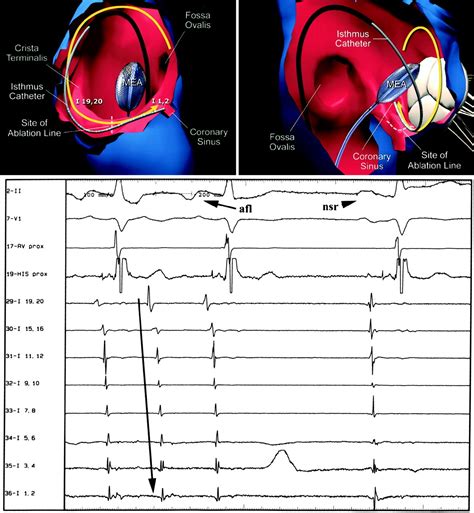

• Mapping: These catheters are guided through the blood vessels into the heart. Sensors at the tip of the catheters record the heart’s electrical activity, creating a 3D map to pinpoint the exact location of the flutter circuit.

• Ablation: Once the site is identified, the doctor delivers radiofrequency energy (heat) or cryoenergy (extreme cold) to the specific area of tissue. This creates a tiny scar that prevents the abnormal electrical signals from circulating.

• Verification: After the ablation, the doctor tests the heart to ensure the flutter can no longer be induced, confirming the success of the procedure.